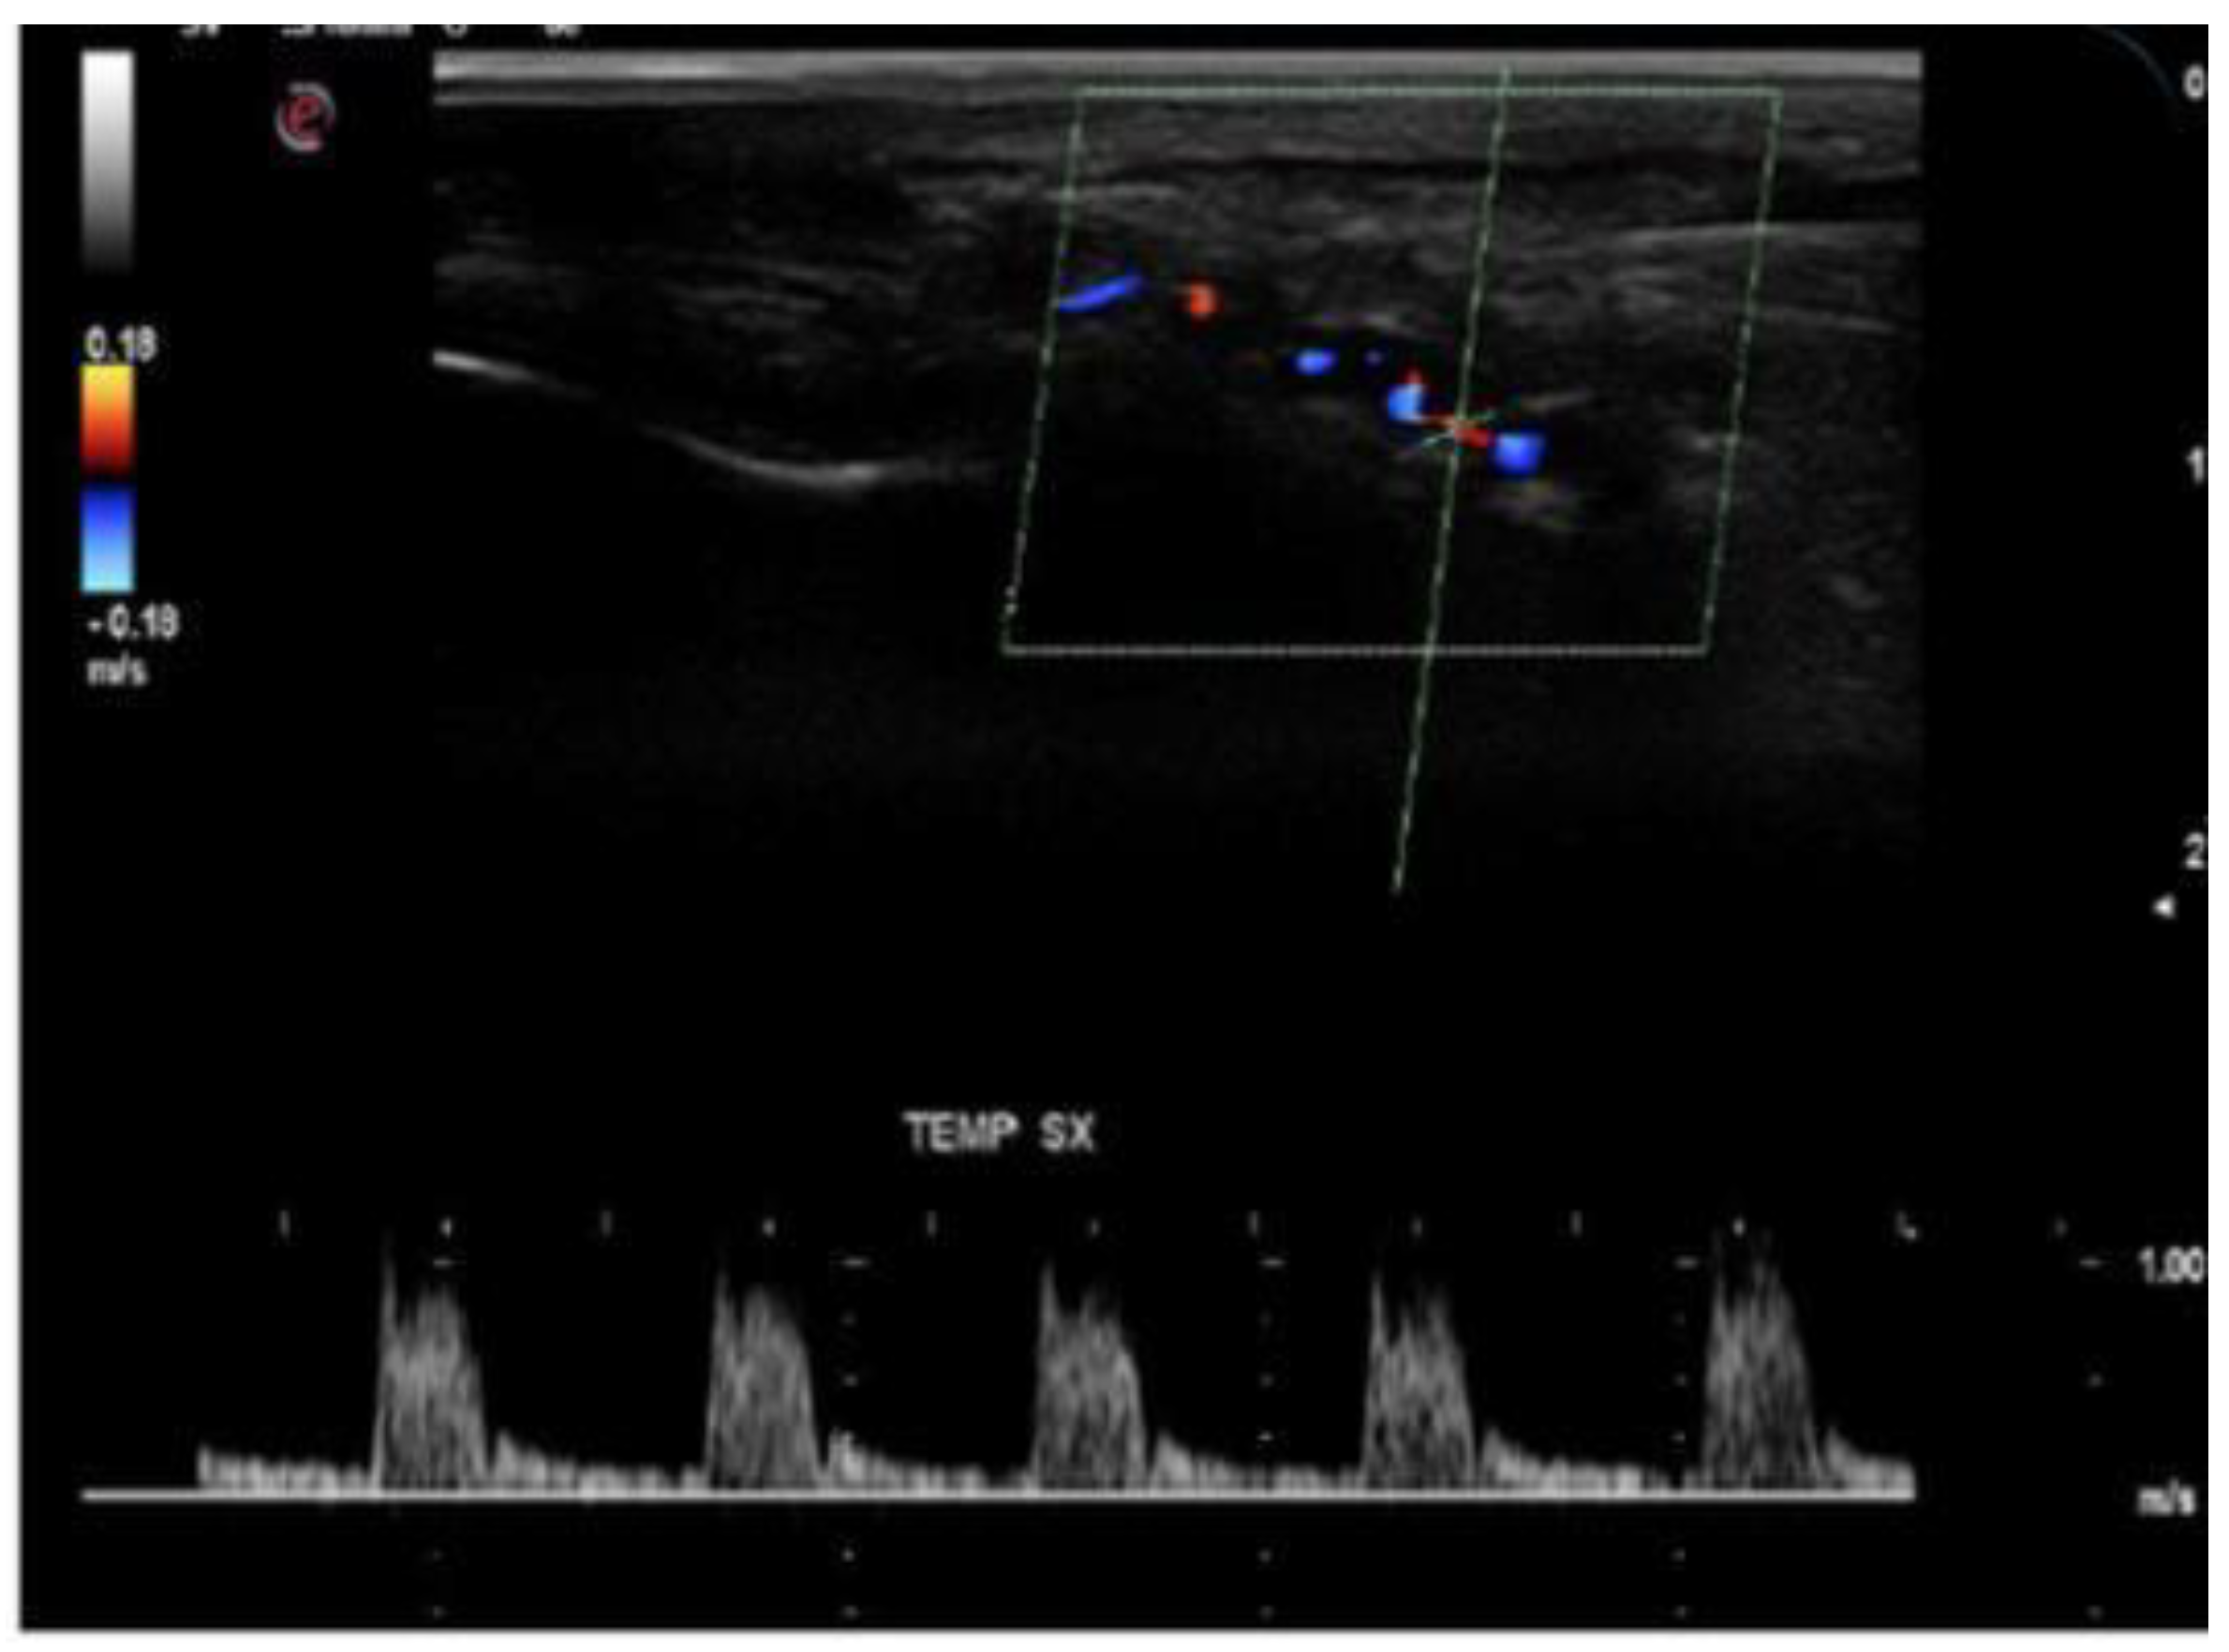

- Stenoses are characterized by aliasing and persistent diastolic flow by colour Doppler US. The peak systolic velocity (PSV) assessed within the stenosis area by pulsed-wave Doppler US is two or more times greater than the PSV recorded in the prestenotic segment of the vessel, with turbulence at the level of stenosis, associated with diminished velocities distal to the stenosis [30,31,32,33,34,35,36,37,38,39,40,41] (Figure 3) [11].

- Acute occlusions, wherein the US image is similar to that of acute embolism in different other vessels, with lack of color Doppler signals (even with low pulse repetition frequency and high color gain) in a visible artery lumen filled with hypoechoic material (cloth) [30,31,32,33,34,35,36,37,38,39,40,41].